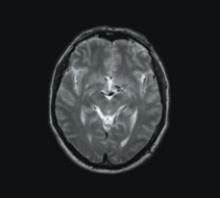

The number of magnetic resonance imaging (MRI) procedures has grown at an average of 10 percent annually over the last 10 years, and there are no signs of stopping as continuous advancements in MR have generated more precise diagnosis for brain and cardiac imaging, bringing it to the forefront of cutting-edge imaging technology.